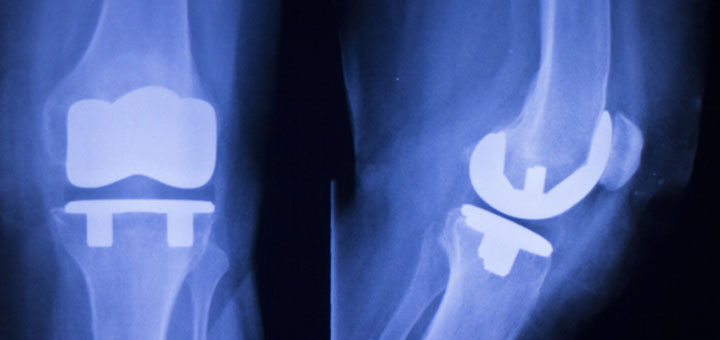

Изделия из УКМ в два с половиной раза легче аналогичных изделий из титана и в 5–7 раз легче изделий из медицинской стали. Эндопротезы суставов из УКМ меньше подвержены разрушениям, в связи с чем расчетный срок их эксплуатации составляет 20–25 лет, тогда как эндопротезы из металлов служат, как правило, пять-семь лет.